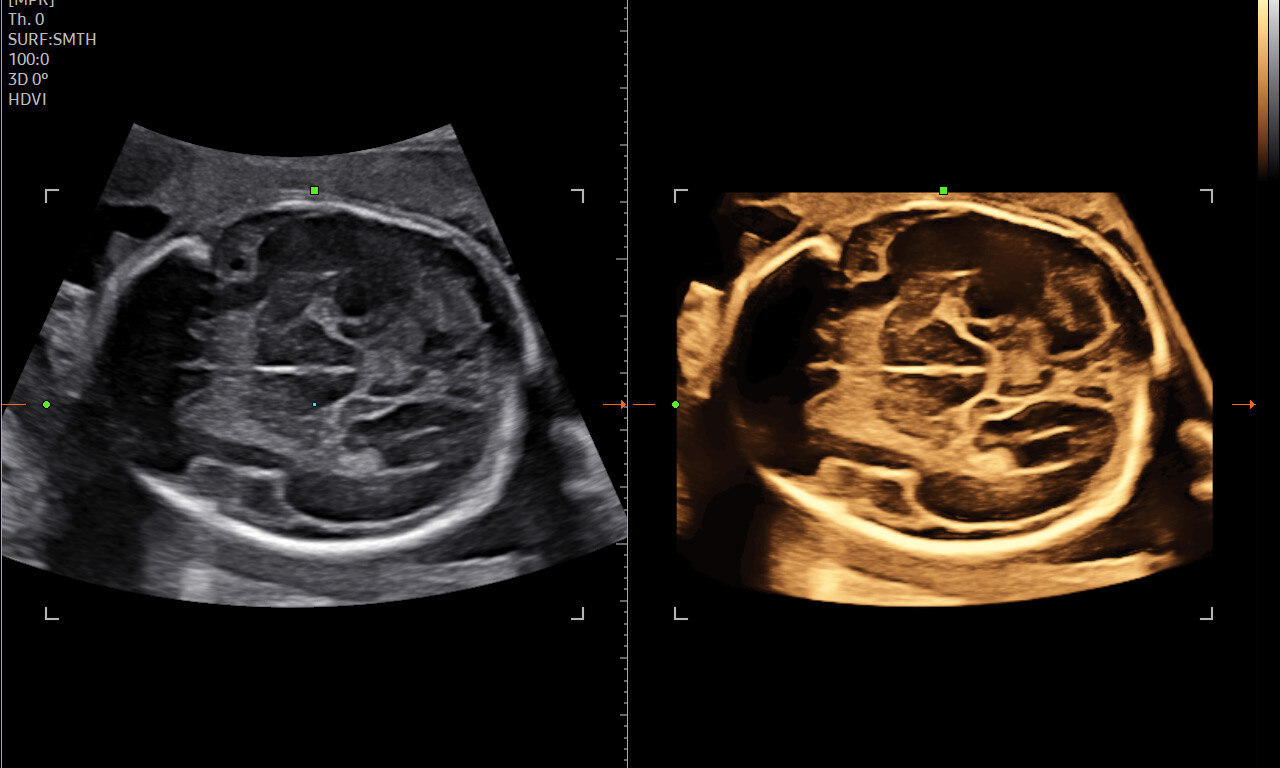

Безупречная картинка в 3D и 4D

Абсолютно новые возможности визуализации с улучшенной системой обработки изображения в режиме 3D и

4D.

- Smart 4D+ — базовый модуль объёмного сканирования (3D + 4D + 3D XI + 3D MXI + HDVI).

- HDVI (High Definition Volume Imaging) — повышение чёткости и контраста границ тканей.

- STIC (Spatio-Temporal Image Correlation) — объёмная динамическая визуализация сердца плода.

- Realistic Vue™ — реалистичная реконструкция 3D-изображения с виртуальным освещением.

- Crystal Vue™ / Crystal Vue Flow™ — прозрачная 3D-визуализация (Flow — объёмный кровоток).

Алгоритм объёмной реконструкции, который формирует реалистичное изображение лица плода. Использует технологию Smart 4D+ и моделирует освещение, чтобы передать глубину и анатомические особенности.

3. HQ Vision™ и ShadowHDR™

HQ Vision делает изображение чётче, а ShadowHDR устраняет тени, возникающие за плотными структурами — например, за черепом или позвоночником плода.